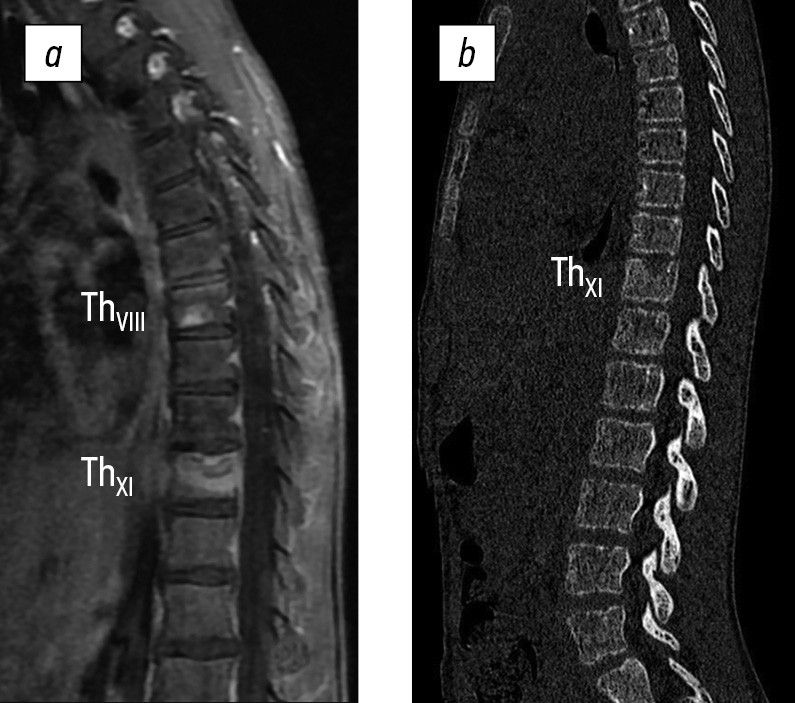

CT findings: A defect with a niche shape measuring 13 × 17 × 7 mm was detected in the middle section of the ThXI vertebral body. The defect destroyed the cranial closure plate and had indistinct, uneven sclerosed contours, and reactive osteosclerosis. In addition, an area of subchondral lucency measuring 4 × 6 mm was found at the cauda terminal plate on the posterior left surface, which caused thinning of the adjacent cortical layer. A homogeneous increase in the densitometric density of the osteosclerosis type was detected in the anterior part of the ThVIII vertebral body, measuring 12 × 8 mm, with a vaguely delineated area of the subchondral lumen of the caudal closure plate up to 4 × 6 mm. In addition, the height of the intervertebral spaces of ThX–ThXI and ThVIII–ThIX decreased. The facet joints at these levels were indistinct. The spinal canal does not exhibit any features. Compared with the previous study of the CT archive, negative dynamics were observed because of the progression of destruction of the ThXI vertebral body and the appearance of new zones of osteolytic changes in the ThVIII and ThXI vertebrae (Fig. 2). CT of the thoracic cavity showed no pathologies.

Fig. 2. Computed tomography of the thoracolumbar spine showing signs of destructive changes in the ThVIII and ThXI vertebral bodies 3 months after disease onset